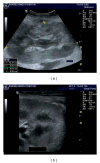

Renal transplantation is the treatment of choice for managing patients with end-stage kidney disease. Being submitted to a very serious surgical procedure, renal transplant recipients can only benefit from follow-up imaging and monitoring strategies. Ultrasound is considered as the principal imaging test in the evaluation of renal transplants. It is an easily applied bedside examination that can detect possible complications and guide further imaging or intervention. In this imaging review, we present essential information regarding the sonographic features of healthy renal transplants, detailing the surgical technique and how it affects the sonoanatomy. We focus on various complications that occur following renal transplantation and their sonographic features by reviewing pertinent literature sources and our own extensive imaging archives.